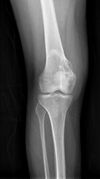

Chondroblastoma[2] Chondroblastoma-distal-femur-2-4.jpg

Cancerous (Chondrosarcoma) Conventional chondrosarcoma grade I (axial skeleton)-III[1][2] Chondrosarcoma (Radiopaedia 23076).jpg